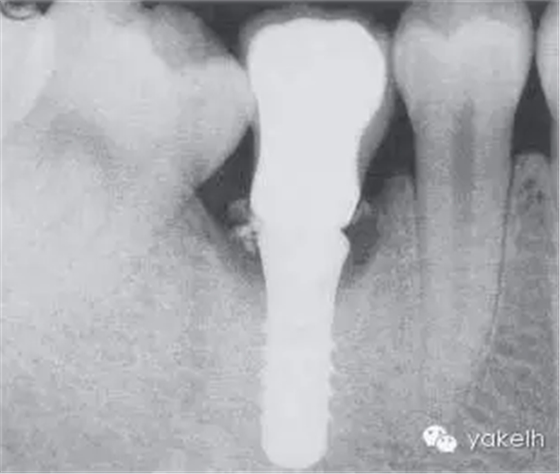

此病例中UR1發(fā)生種植體周圍炎,導(dǎo)致嚴(yán)重的美學(xué)問題。種植體周圍黏膜退縮,種植體頸部金屬暴露(圖.10A)。種植體唇側(cè)組織感染、腫脹,存在深牙周袋。影像學(xué)檢查顯示種植體周圍大面積骨喪失(圖.10B)。

圖.10 種植體植入位置不恰當(dāng),導(dǎo)致種植體周圍炎。